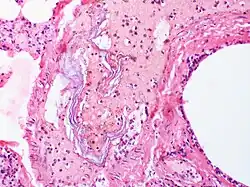

Intravascular squames are present in this example of amniotic fluid embolism.